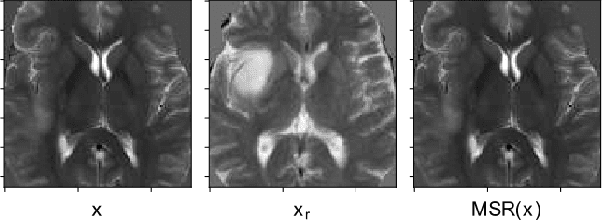

Abstract:Automatic brain tumor segmentation from Magnetic Resonance Imaging (MRI) data plays an important role in assessing tumor response to therapy and personalized treatment stratification.Manual segmentation is tedious and subjective.Deep-learning-based algorithms for brain tumor segmentation have the potential to provide objective and fast tumor segmentation.However, the training of such algorithms requires large datasets which are not always available. Data augmentation techniques may reduce the need for large datasets.However current approaches are mostly parametric and may result in suboptimal performance.We introduce two non-parametric methods of data augmentation for brain tumor segmentation: the mixed structure regularization (MSR) and shuffle pixels noise (SPN).We evaluated the added value of the MSR and SPN augmentation on the brain tumor segmentation (BraTS) 2018 challenge dataset with the encoder-decoder nnU-Net architecture as the segmentation algorithm.Both MSR and SPN improve the nnU-Net segmentation accuracy compared to parametric Gaussian noise augmentation.Mean dice score increased from 80% to 82% and p-values=0.0022, 0.0028 when comparing MSR to non-parametric augmentation for the tumor core and whole tumor experiments respectively.The proposed MSR and SPN augmentations have the potential to improve neural-networks performance in other tasks as well.

Abstract:Deep sparse auto-encoders with mixed structure regularization (MSR) in addition to explicit sparsity regularization term and stochastic corruption of the input data with Gaussian noise have the potential to improve unsupervised abnormality detection. Unsupervised abnormality detection based on identifying outliers using deep sparse auto-encoders is a very appealing approach for medical computer aided detection systems as it requires only healthy data for training rather than expert annotated abnormality. In the task of detecting coronary artery disease from Coronary Computed Tomography Angiography (CCTA), our results suggests that the MSR has the potential to improve overall performance by 20-30% compared to deep sparse and denoising auto-encoders.